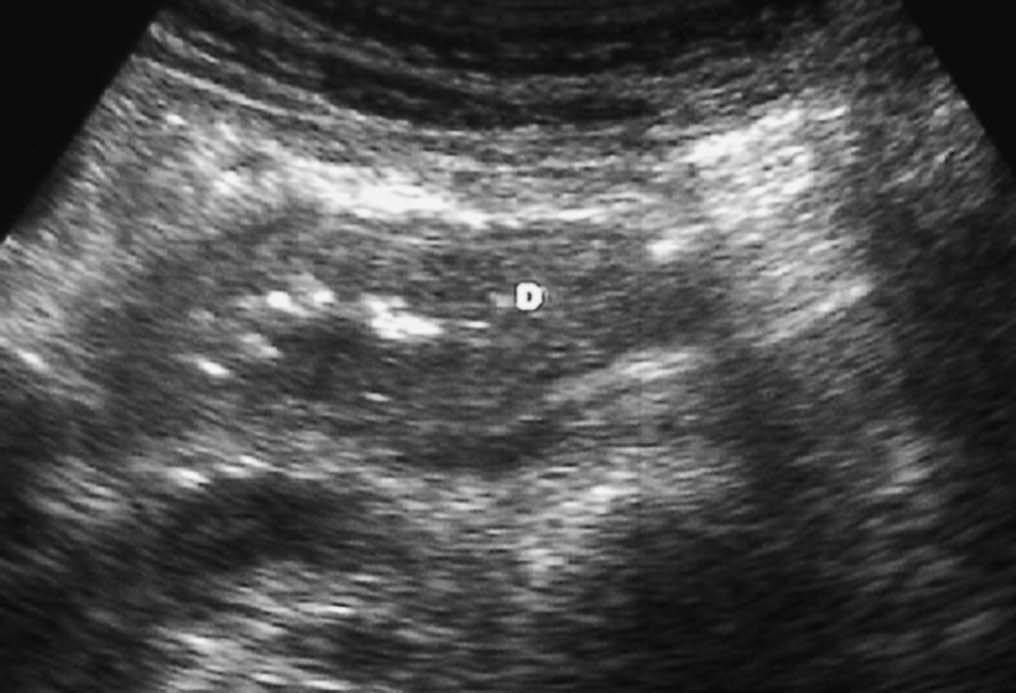

Una complicación tardía de la pancreatitis es el pseudoquiste. Puede localizarse en la pared duodenal, donde aparece radiológicamente como una lesión quística de paredes bien definidas, pudiendo producir una estenosis luminal (fig. 11).

Fig. 11--Pseudoquiste en pared duodenal. (A) Ecografía. (B) Tomografía computarizada en la que se aprecia una lesión quística (flecha) en la pared posterior de la tercera porción duodenal, que provoca compresión de la luz.